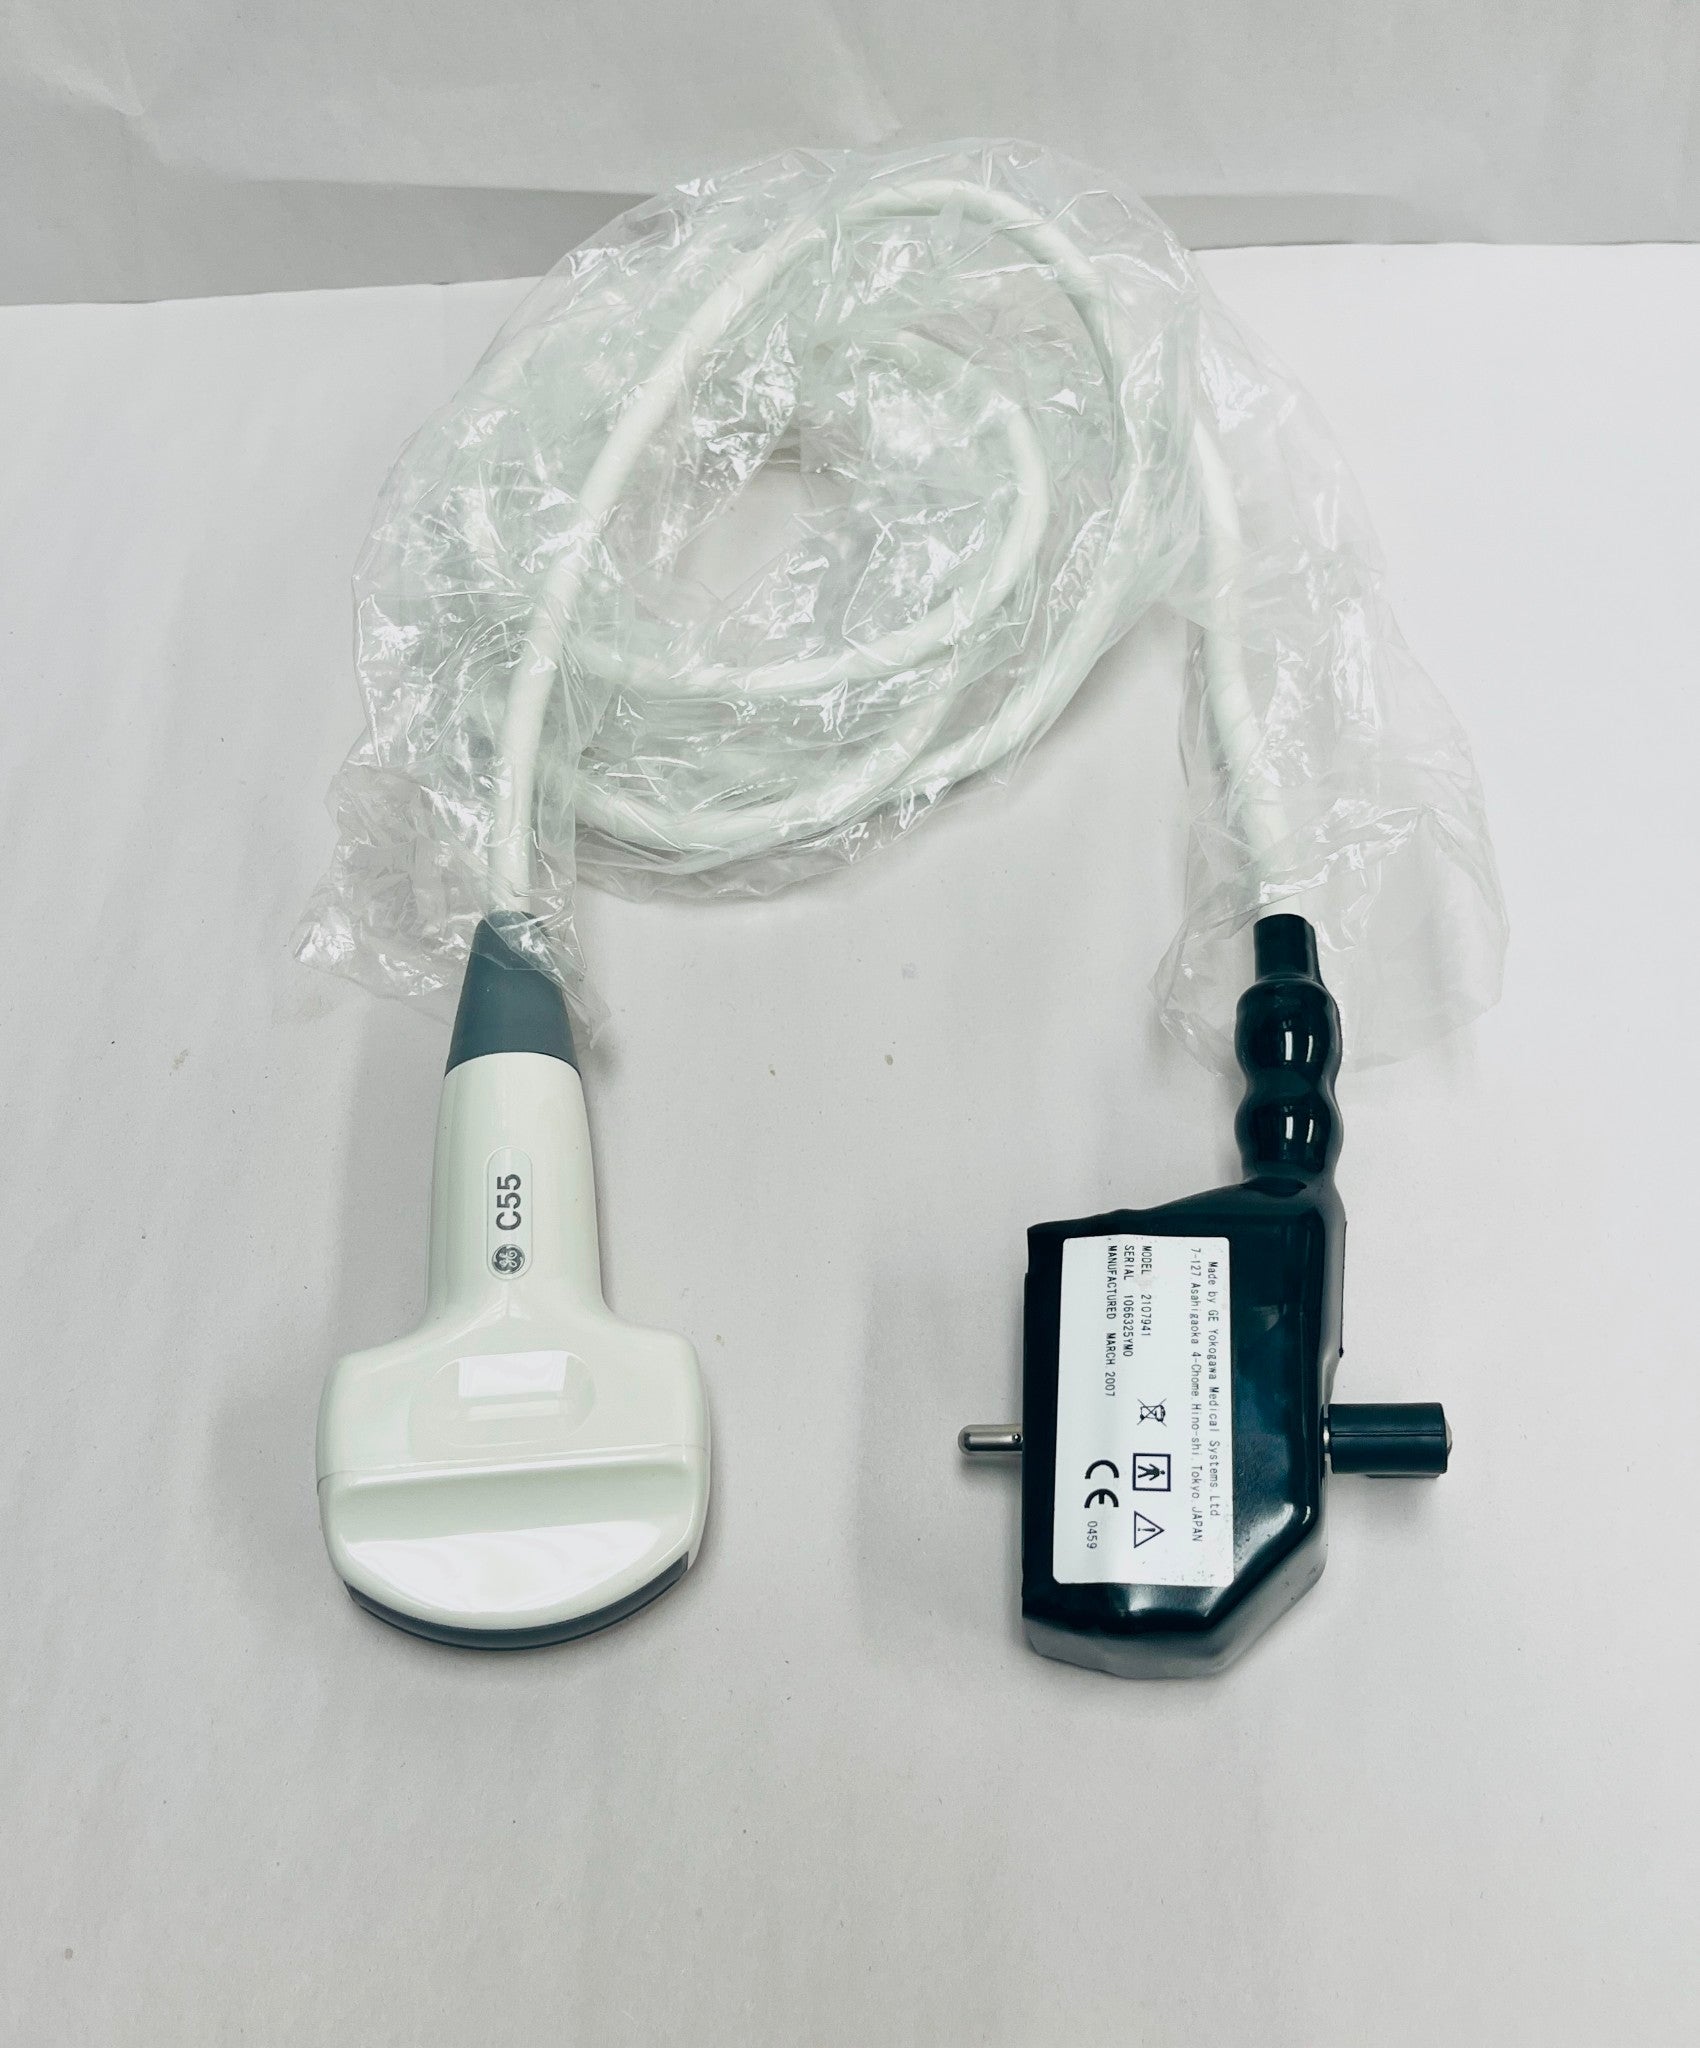

DIAGNOSTIC ULTRASOUND MACHINES FOR SALE

GE 6S Ultrasound Probe Transducer DOM 2012

Sale price$ 2,229.28